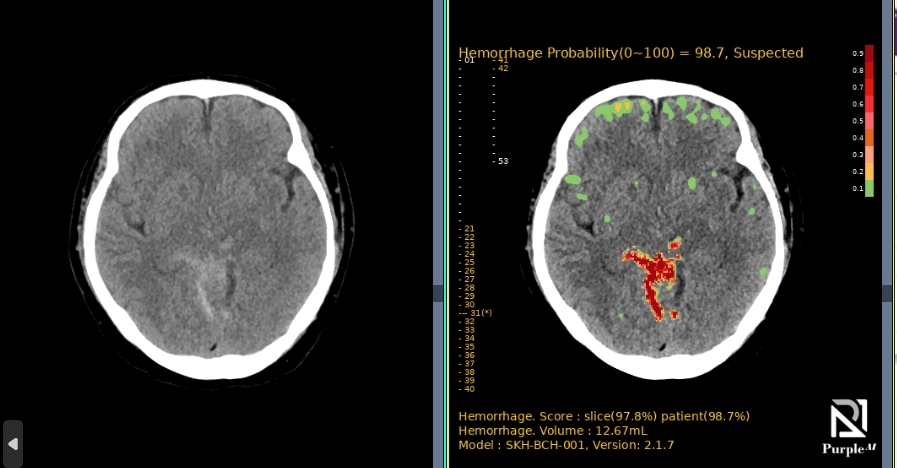

Download BrochureAI-powered diagnostic support for rapid, accurate detection and localization of brain hemorrhages on non-contrast CT, with ROI visualization and volume quantification to help radiologists assess hemorrhagic regions.

A multi-center, randomized, retrospective crossover superiority pivotal study, demonstrating high performance across all major ICH subtypes.

| Trial Size | 394 brain CT images (198 positive / 196 negative cases) |